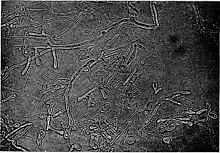

Blastomyces is a genus of fungi in the order Onygenales. Species are known human pathogens and show thermal dimorphism, converting from hyphal states under saprobic conditions to yeast-like states under pathogenic conditions. They are the causative agents of blastomycosis, a systemic mycosis in immunocompromised patients.[1][2]